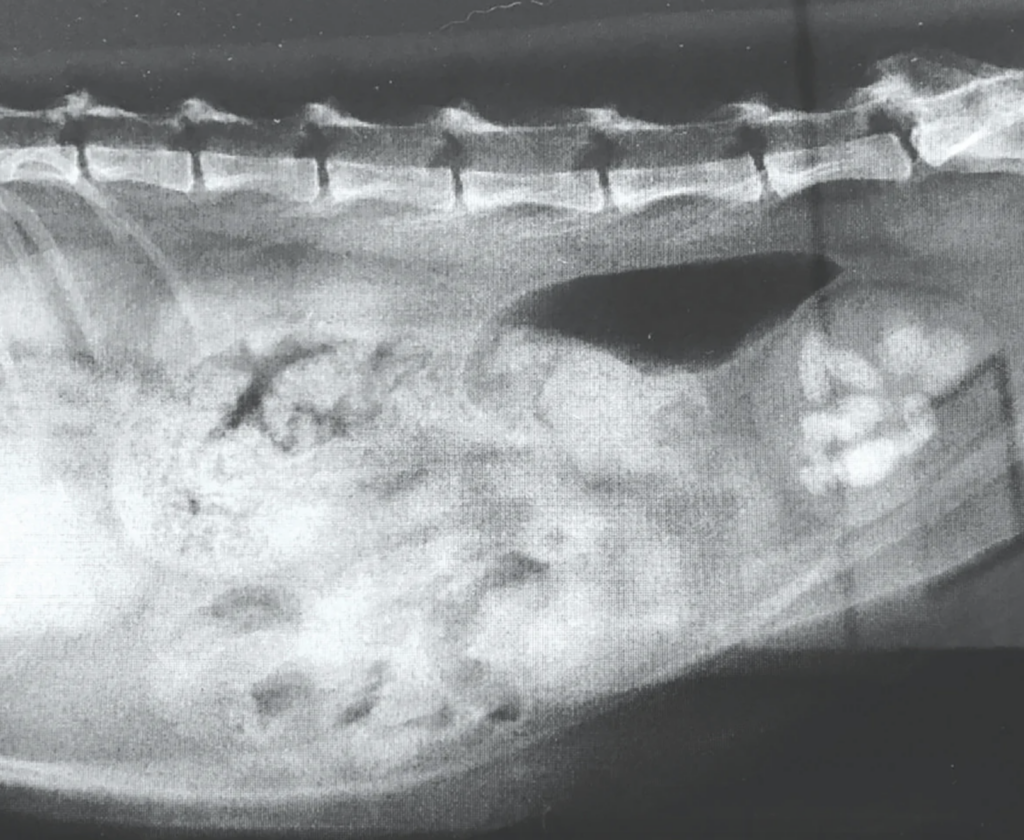

Seterusnya, imbasan ultrasonik akan dijalankan untuk memeriksa keadaan dinding pundi kencing dan mengesahkan kehadiran batu karang.

Imbasan radiografi kontras juga mungkin diperlukan untuk melihat kedudukan dan saiz batu karang.